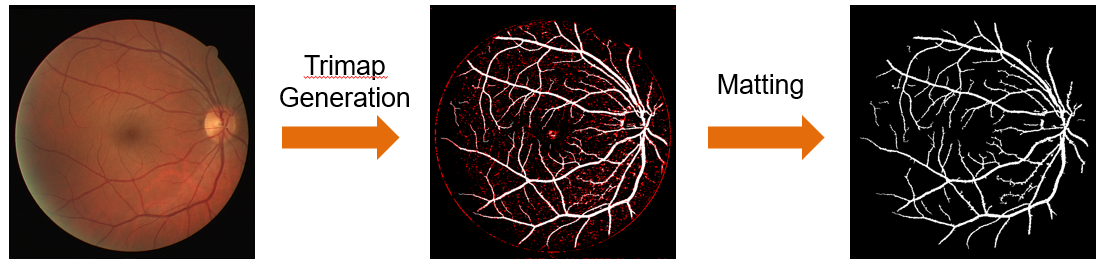

图一 基于分层抠图模型的血管分割算法总体流程 如图一所示,基于分层抠图模型的血管分割算法流程由三分图的生成(Trimap Generation)[4]和抠图(Matting)两步组成。在三分图生成中,为了提高血管的对比度,我们采用小波变换和形态学处理对血管的整体特征进行增强,然后结合阈值处理和血管的形状特征实现图像的分割和血管的主干部分提取,进而获得眼底图像的三分图。下面给出了三分图生成流程和实例展示,如图二所示。

图二 三分图的生成流程和实例展示 在抠图环节提出了分层抠图模型,实现三分图的进一步分割。下面给出了分层抠图模型的算法框架和实例展示,如图三所示。该算法主要分为两步: 对未知像素点的分层(Stratifying the unknown pixels)和分层更新(Hierarchical Update)。